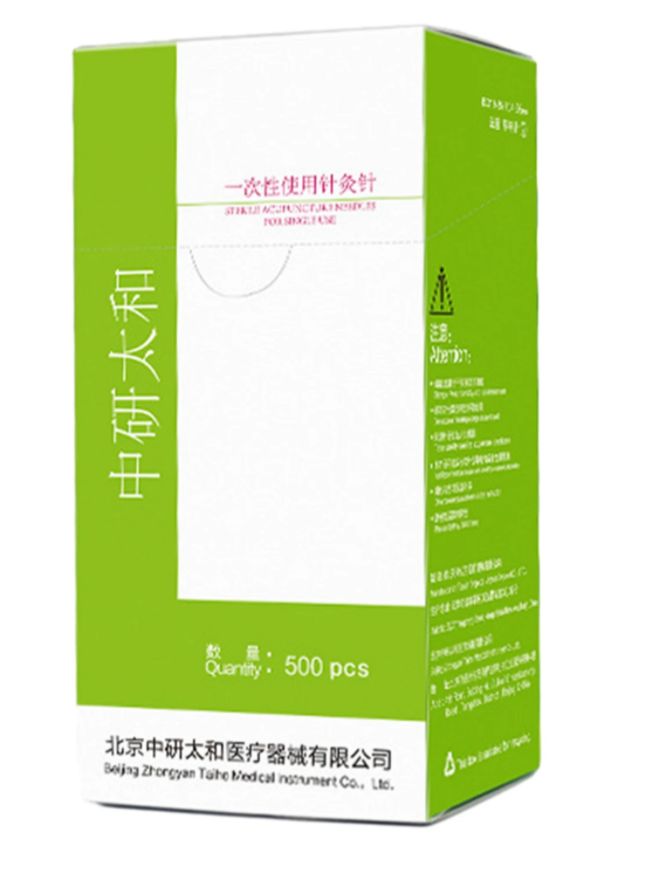

DISPOSABLE ACCUPUNCTURE NEEDLE

DISPOSABLE ACCUPUNCTURE NEEDLE